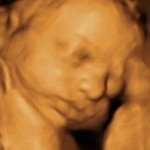

4D/5D/HD Ultrasound Gallery

Gallery